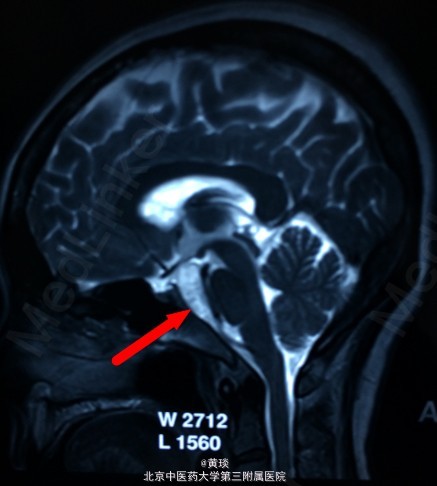

患者女,75岁,自诉压槽疼痛10年,未予重视,曾行封闭治疗无效,来我院,本来诊断为普通三叉神经痛,结果行MRI示:桥小脑角区占位,胆脂瘤,T1相高信号,T2相低信号,抑脂相高信号,压迫右侧三叉神经。

见图

诊断:胆脂瘤,继发三叉神经痛 处理:开颅切除胆脂瘤